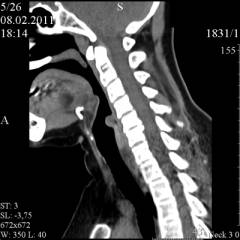

Компьютерная томография (КТ) и магнитно-резонансная томография (МРТ) КТ и МРТ – современные методы диагностики, при помощи которых можно получить качественное трехмерное изображение или послойные срезы органа.

При помощи КТ и МРТ можно определить:

• положение опухоли;

• размеры;

• распространенность;

• прорастание в соседние органы;

• метастазы в лимфатические узлы.

Эти методики позволяют получить более точную картину по сравнению с рентгенографией.

Принципы проведения КТ и МРТ схожи. Пациента укладывают в специальный аппарат, в котором он должен находиться неподвижно в течение определенного времени.

Оба исследования безопасны, так как отсутствует лучевая нагрузка на организм пациента (МРТ), либо она минимальна (КТ).